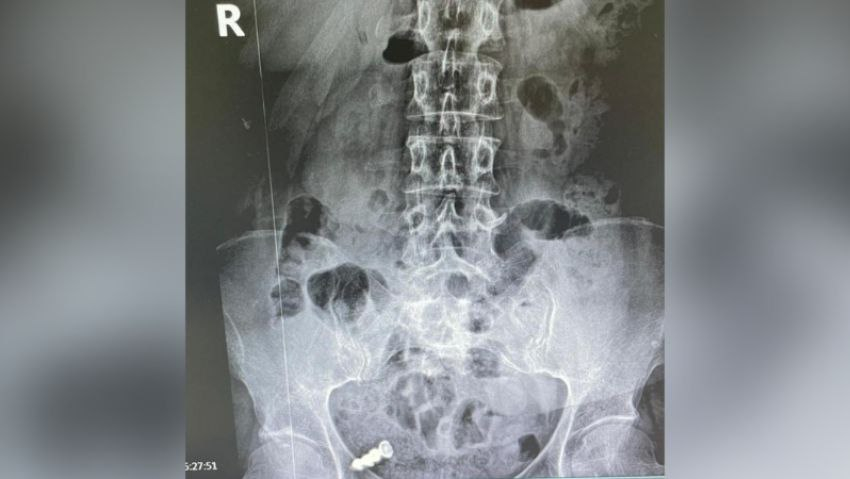

Женщина случайно проглотила съемный зубной протез, забыв снять его перед сном